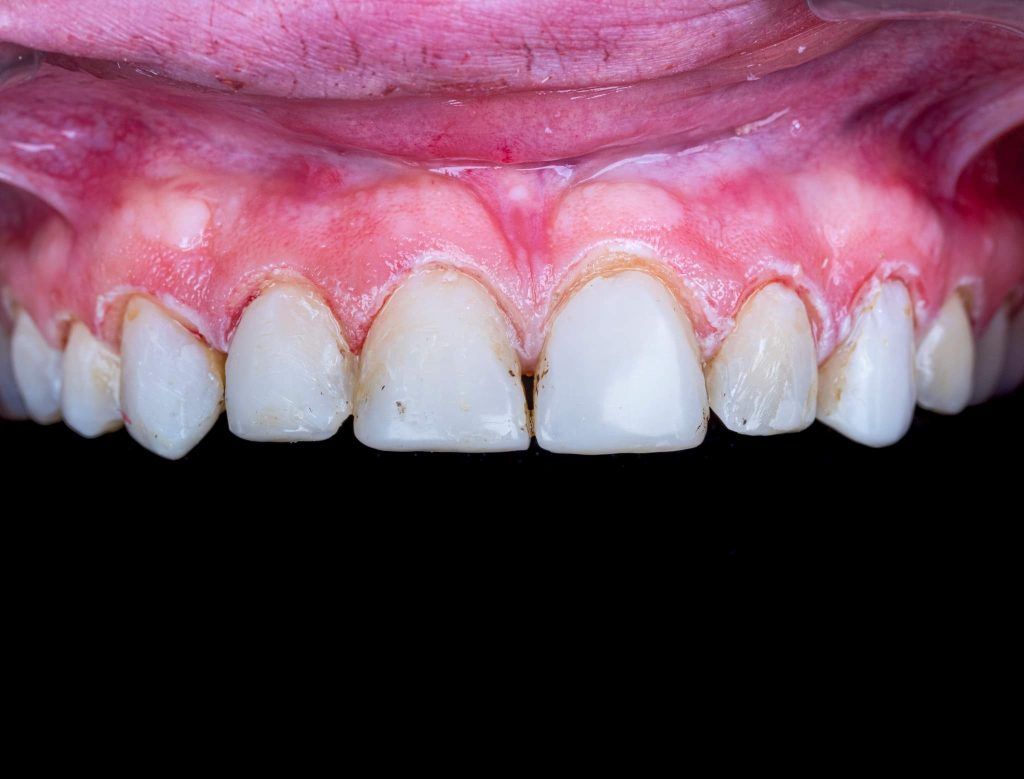

The case presented in this case report is for a 27-years-old female patient with a chief complaint of aesthetic correction for her smile. The patient was unhappy with her smile. After clinical examination, there were previous old composite veneering done poorly and incorrectly to close the multiple interdental spacing. After discussing the various treatment options (i.e., orthodontic treatment, direct, or indirect veneers), indirect ceramic veneering was selected. The step-by-step treatment protocol is presented in the images below.